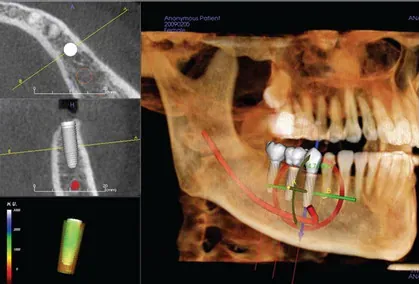

Bringing Your Smile To The Next Step With Computer-Guided Technology

In computer-guided dental implant surgeries, a 3D cone-beam scan is used to perform a virtual surgery in which a 3D scan is overlaid on a patient’s mouth and the surgeon performs a virtual and simulated procedure before proceeding with the actual one. A computer-generated surgical guide is created from the information gathered from the simulation to assist in the precise placement of the dental implants. This allows the surgeon to do a trial run and master whatever steps are necessary to make the surgery a success.

Computer-guided implant surgery is helpful in cases where margin of error is small and where a free-hand procedure might possibly lead to a negative outcome. It’s also helpful in cases where there is little to no landmarks to help guide the orientation of the teeth.